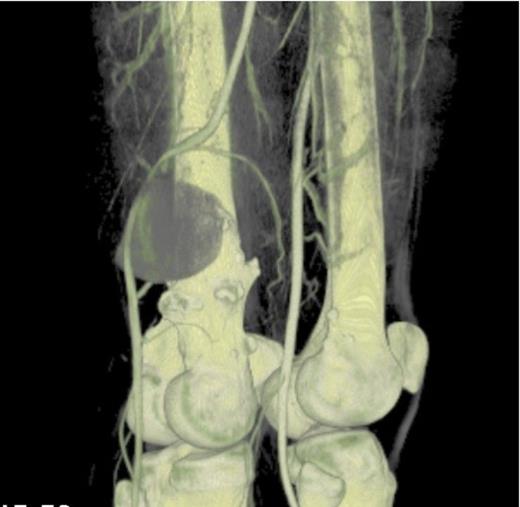

An ultrasound concluded an 8.8cm pseudoaneurysm and the patient was admitted for urgent pre-op CT angio (figure 3 and 4) and surgical exploration.

CT angiogram 3D reconstruction- Showing the bony exostoses and the popliteal aneurysm posterior to the right distal femur

CT angiogram: Showing the diameter size of the aneurysm to be 88.6mm. The cross sectional image clearly shows the sharp bony exostoses that slowly eroded into the popliteal artery resulting in the pseudoaneurysm formation. The image also shows that the defect in the artery is still patent because the pseudoaneurysm is filling with contrast